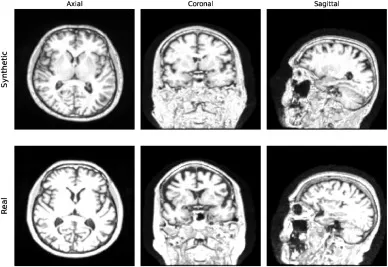

本研究首先通过定性(图2)和定量(表1、表2)分析评估了合成MRI图像的质量。结果显示,合成图像具有高真实感,且记忆化问题不明显,最高相关性(0.79)甚至低于AIBL与真实ADNI数据集之间的相关性(0.8)。在AD诊断任务中,在3T ADNI数据集上,基于合成数据预训练的2D ADnet模型在CN/AD二分类任务中取得了91.3%的准确率,优于基线模型28.8个百分点,并比最先进方法高8.8个百分点。在CN/MCI/AD三分类任务中,2D ADnet达到了74.5%的准确率和74.2%的F1分数,同样显著优于基线模型和ImageNet预训练模型。值得注意的是,使用合成数据预训练的模型性能与使用真实数据预训练的“Oracle”模型(数据量是合成数据的四倍)仅有0.3个百分点的差距。在OASIS-2数据集的ND/C/D分类任务中,我们的最佳模型达到了59.3%的准确率和57.6%的F1分数,超越了所有竞争模型。消融研究进一步表明,合成数据预训练在不同数据集大小下均能保持稳定的高性能,并且始终优于使用真实数据进行的预训练;同时,预训练的模型在不同微调数据集大小下都表现出更高的鲁棒性,并持续优于从零开始训练的模型。

图3.不同解剖视图中最高相关性分布的比较。每列对应一个特定的MRI视图:轴位(左)、冠状位(中)和矢状位(右)。 (上排)合成图像与1.5T ADNI之间的相关性分布,按诊断类别(CN、MCI、AD)分组。(下排)合成图像与1.5T ADNI图像(蓝色)以及AIBL与1.5T ADNI数据(橙色)之间的相关性比较。

图4.不同解剖视图中最高相关性分布的比较:合成图像(顶行)和最相关的真实图像(底行)。